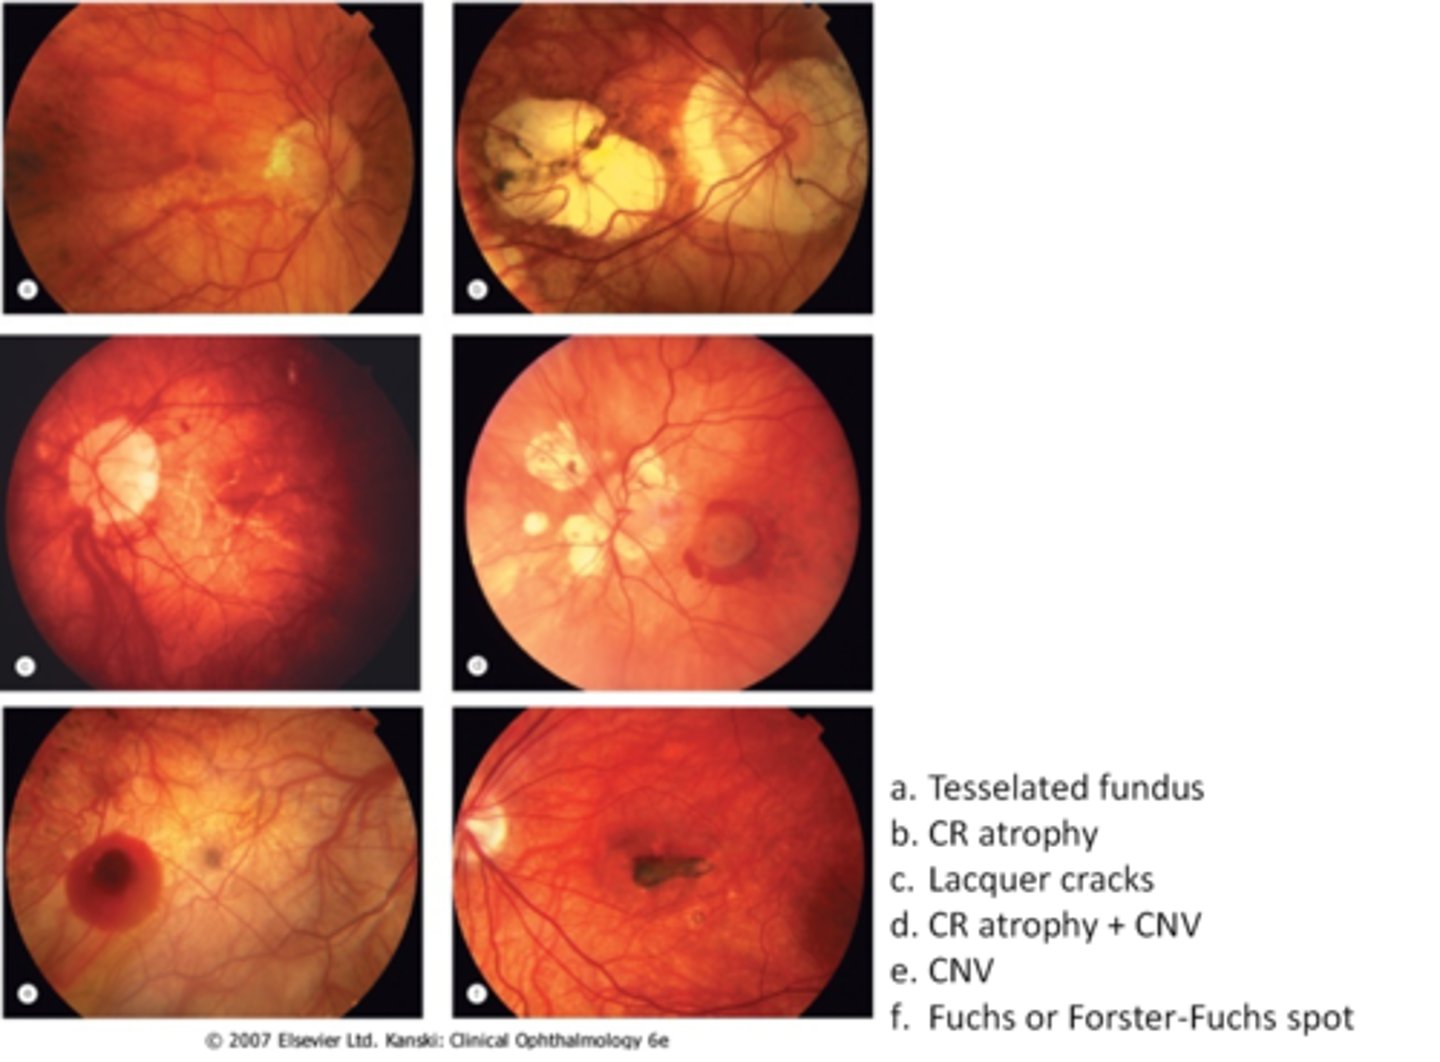

tesselated or tigroid fundus = visibility of choroidal vasculature (A)

What are some common findings in degenerative myopia?

lacquer cracks (C)

CNV (E)

chorioretinal atrophy (B)

What findings of degenerative myopia are seen here?

PPA

crescent

lacquer cracks

How do lacquer cracks appear on fundoscopy?

jagged, irregular yellow lines showing sclera in the posterior pole